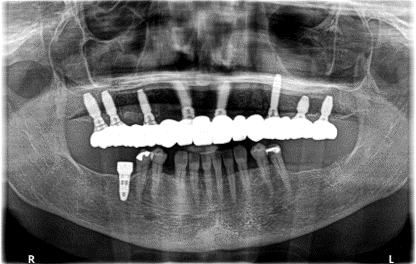

Dental X-ray showing multiple dental implants and crowns in upper and lower jaw.